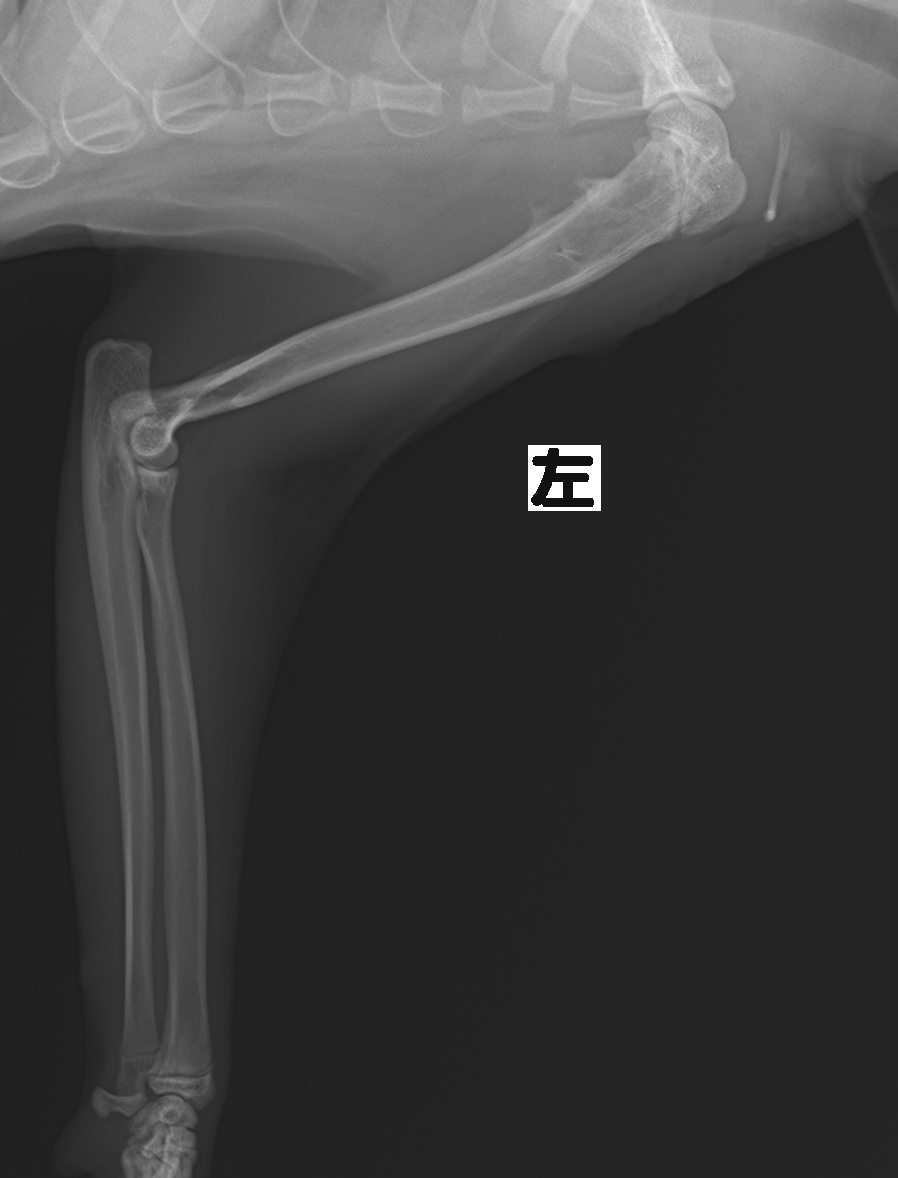

術後2ヶ月半後のレントゲン写真です。

骨折ラインはほぼ消失したので、ピンとワイヤーを抜く手術を行いました。

抜ピン直後のレントゲン写真です。